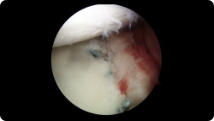

Arthroscopic image of a shoulder dislocation Arthroscopic image of a repaired shoulder dislocation

Shoulder Dislocation Repair